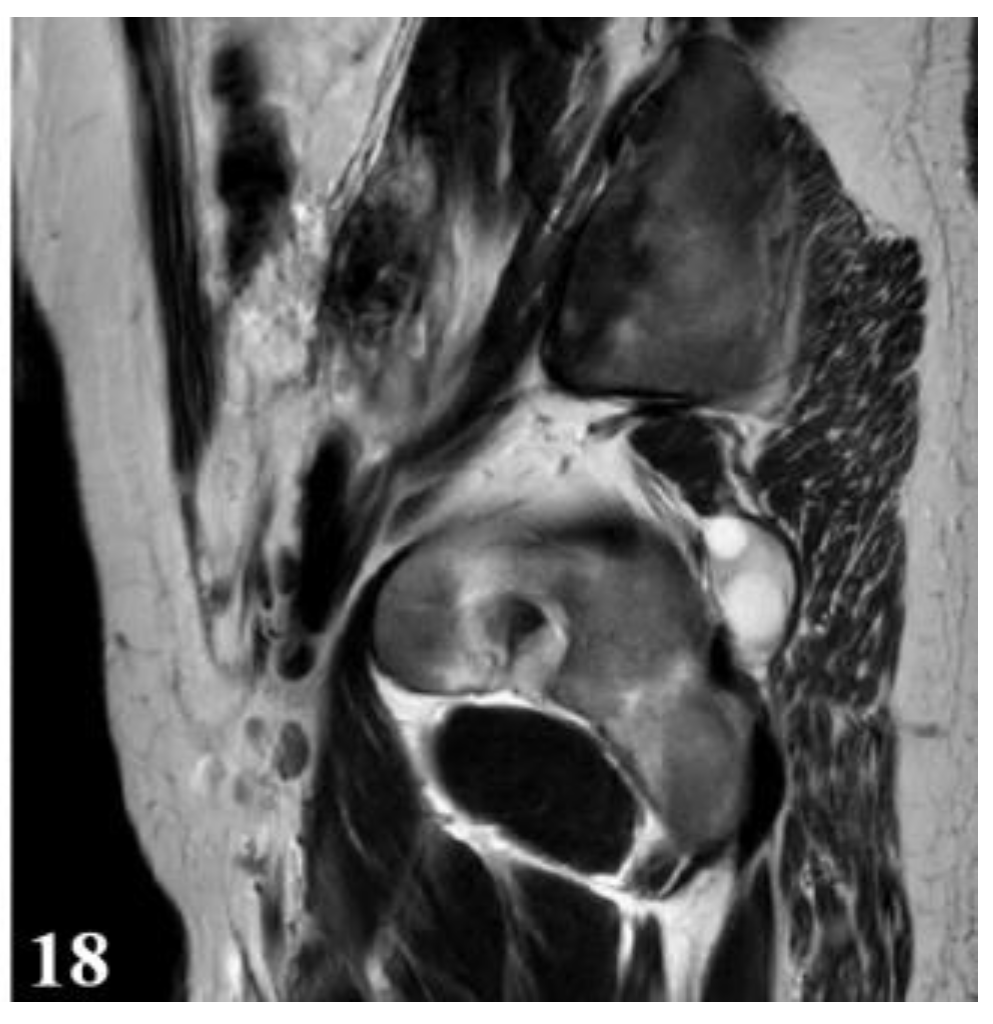

Figure 18.

T2W sequence, sagittal—Postoperative residual hydatid cyst located at the level of the left iliopsoas muscle and deep to the left gluteus maximus muscle (part 2).

Considering the impossibility of performing an ideal cystectomy, it was decided to perform an efficient drainage by closing the remaining retroperitoneal cavity after mounting a drain tube (through which the lavage and drainage slope at the base of the left thigh with tubes passed through the muscle gap is carried out). Adjacent peritoneal drainage and anatomical parietorrhaphy. Native MRI examination and post-operative intravenous post-contrast (Figure 17 and Figure 18), reveals: diffuse infiltrative-edematous appearance at the level of the iliopsoas muscle on the left side, with the presence of a collection with peripheral type gadophilia, difficult to appreciate under dimensional ratio, with a tendency to diffuse extension, developed predominantly intramuscularly at the level of the psoas muscle on the left side, with the predominant interest of its peripheral portion between 7–3 o’clock (being tangent to the external iliac vessels on the left side, with present, homogeneous flow at their level), extended to at the level of the ipsilateral iliac muscle and later in a caudal direction at the level of the iliopsoas muscle on the left side up to the vicinity of its distal insertion, after which it insinuates between the muscles of the antero-internal region of the thigh on the left side up to the border between the proximal third and the middle third of the thigh, and coming into contact on several sections with the femoral vessels on the left side, but without causing changes in caliber or flow at their level. At the level of the proximal portion there is a fistulous tract with a maximum thickness of approximately 0.7 cm, externalized at the level of the root of the left thigh in the antero-internal region which seems to communicate in depth with the previously described collection. In the proximal portion of the thigh on the left side, diffuse infiltrative-edematous changes adjacent to the previously described collection are evident at the level of the intermuscular space in the anterior region of the thigh, without being accompanied by similar changes at the level of the muscles in the anterior region of the thigh (Figure 17 and Figure 18).

Deep from the gluteus maximus muscle on the left side, there are multiloculated, multiple septate intralesional, relatively well delimited areas, which seem to communicate both with each other and with lesions of a similar appearance located in the thickness and adjacent to the quadratus femoris muscle on the left side, with total dimensions in the coronal plane of approximately 11.3/6.4 cm, with the most likely appearance of parasitic cysts (Figure 19, Figure 20 and Figure 21).